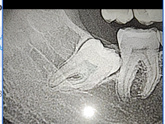

Как считаете, стоит ли удалять? Корни проходят через нервы, т.е.будут последствия. Была у нескольких врачей, говорят решать мне. Возможно он так и будет, а возможно и разрушится со временем и будет воспаление(за последние несколько лет все жевательные … Читать далее